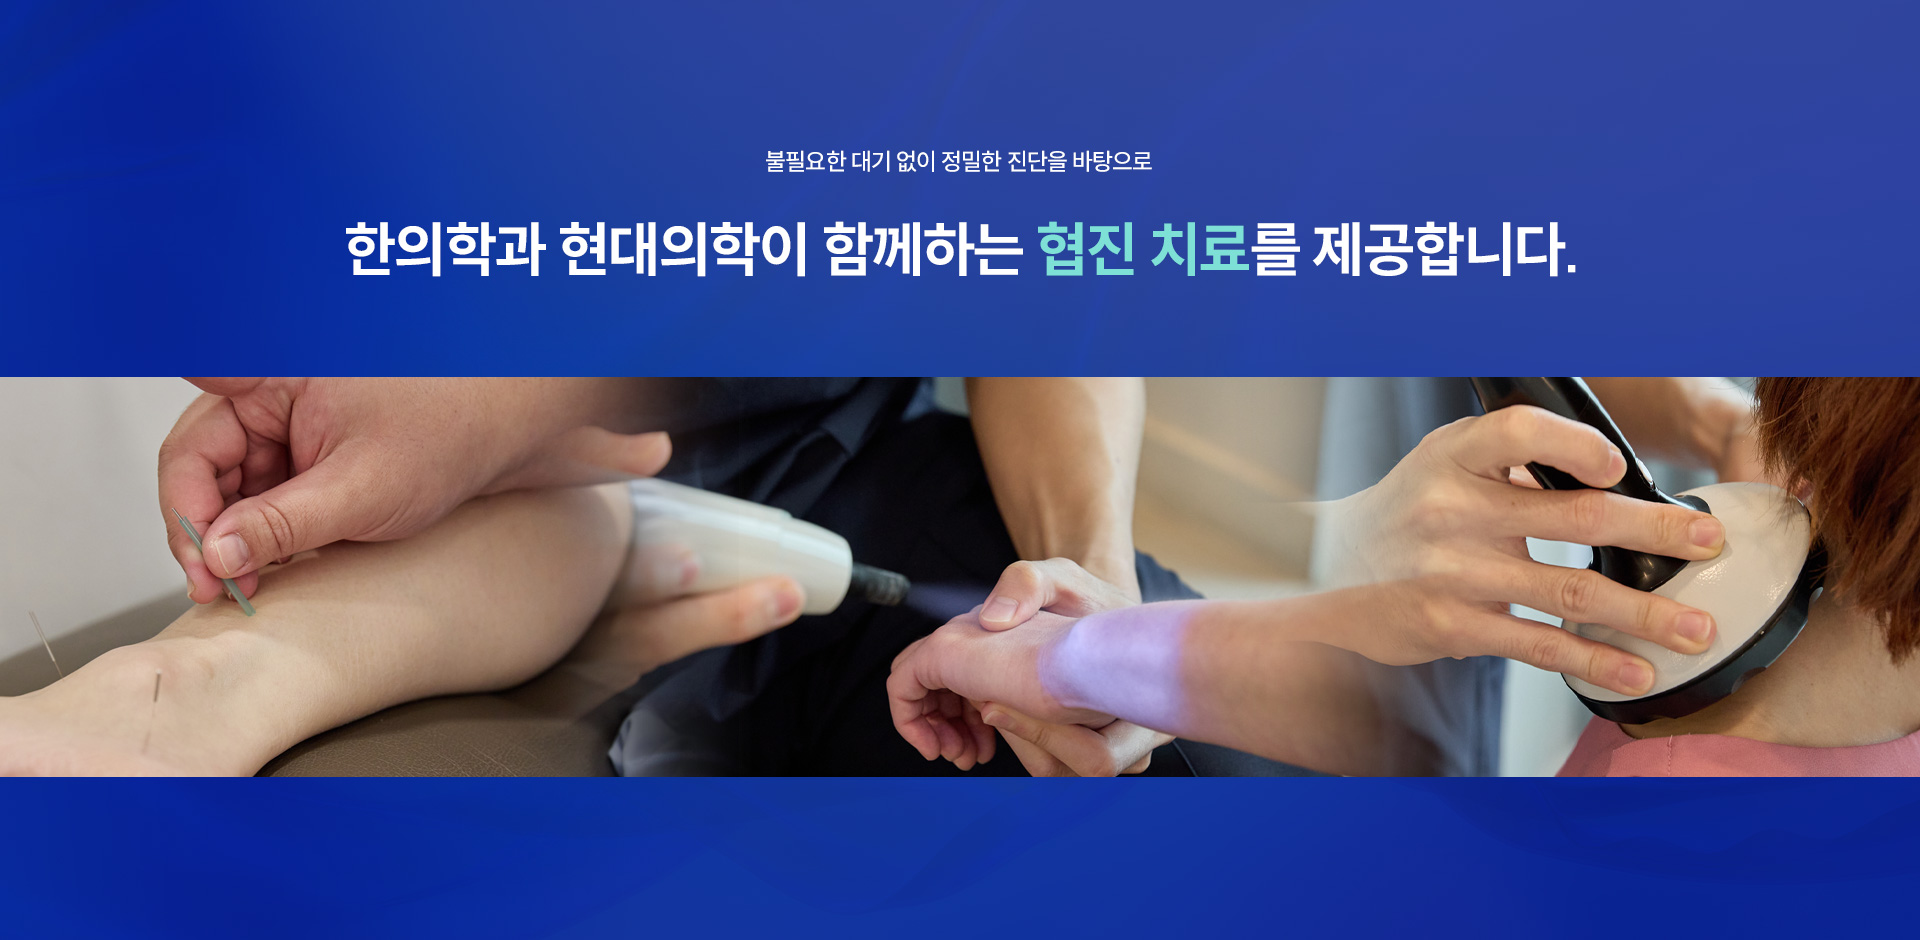

계속 반복되는 소화불량, 한방 치료로 해결할 수 있을까요?

네, 담적은 위장의 운동 기능 저하, 기혈 순환 정체, 자율신경계 불균형 등의 기능 이상을 의미합니다.

1.담적을 배출, 2. 위장운동력을 회복, 3. 자율신경 안정과 회복을 돕습니다.